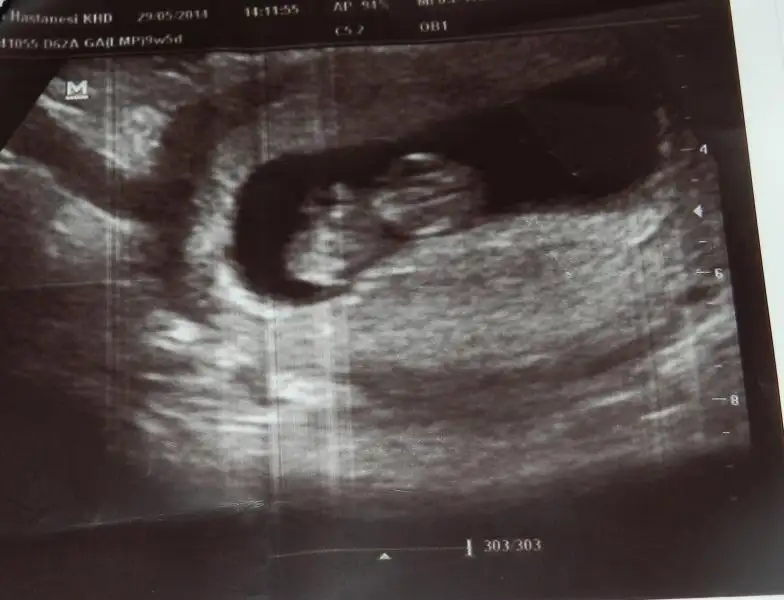

Benim 4 boyutlu değil ama bakabilirmisiniz nubuna. Şu an 13+0 Daha 10 gün var kontrole. Ilkinde 11 hafta 5 gün,ikincisinde 12 hafta 3 günlüktük.

$ImageUploadedByKadınlar Kulübü1403871661.181270.webp